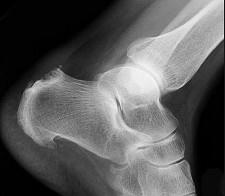

女,52岁,足跟痛,手指运动僵硬,请结合影像图像,选择最可能的诊断 ( )A、骨折B、类风湿关节炎C、骨脓肿D、骨囊肿E、骨质疏松

问题 女,52岁,足跟痛,手指运动僵硬,请结合影像图像,选择最可能的诊断 ( )

选项 A、骨折 B、类风湿关节炎 C、骨脓肿 D、骨囊肿 E、骨质疏松

答案 B